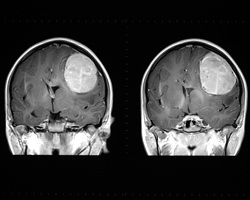

L'imagerie médicale est un outil essentiel dans les environnements cliniques, en particulier la mise au point d'outils d'imagerie quantitatifs dans le cadre des traitements du cancer et de la mesure de la réponse tumorale après le traitement. Le projet MICAT («Medical image analysis for cancer treatment monitoring and tumor atlas formation») a travaillé sur la mise au point de nouvelles méthodes de calcul médical et sur un cadre pour l'analyse des images médicales permettant d'assurer une surveillance pendant le traitement du cancer. Le projet MICAT était axé en particulier sur l'évaluation de la réponse tumorale et sur l'élaboration d'un nouvel atlas probabiliste pour les tumeurs cérébrales. La segmentation des tumeurs à partir de données d'imagerie est difficile en raison de l'aspect très varié du tissu tumoral selon les patients et, dans certains cas, par rapport à des tissus normaux. L'équipe du projet MICAT a mis au point une méthode de segmentation basée sur l'algorithme des automates cellulaires. Les études de validation ont permis de démontrer que l'algorithme final surpassait les algorithmes «graph cut» et «grow cut», avec une sensibilité plus faible à l'initialisation et au type de tumeur. Les applications d'enregistrement des images permettent de combiner des images d'un même sujet à partir de différentes modalités et d'assurer le guidage par images lors des interventions. Les chercheurs du projet MICAT ont mis au point une nouvelle méthode d'enregistrement rigide fondée sur des points de repère anatomiques dans le cerveau afin de comparer les images de référence et de suivi de la tumeur cérébrale d'un patient. La nouvelle technique met en œuvre des images par résonance magnétique à pondération T1 avec produit de contraste. Les scans à pondération T1 permettent de représenter les différences de temps de relaxation spin-milieu du tissu. Les nouveaux protocoles permettent d'améliorer la précision et la fiabilité des mesures de l'évolution du volume et du diamètre de la tumeur. En outre, les membres de l'équipe du projet MICAT étudient de nouveaux critères locaux à l'aide du tenseur des déformations de Lagrange. À ce jour, sept articles détaillant les réalisations du projet MICAT ont été publiés. Les outils logiciels seront mis à la disposition des cliniques, ce qui permettra d'accroître l'efficacité de la radiochirurgie des tumeurs et l'analyse de la réponse tumorale cérébrale pour le suivi après traitement.